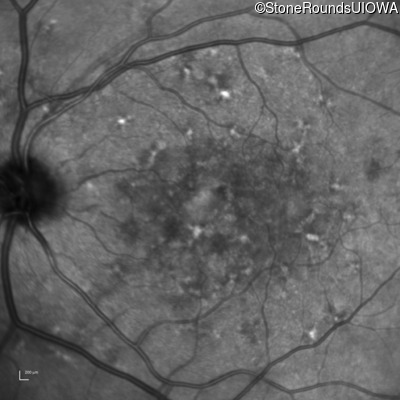

Infrared Fundus Photograph - Right - 20/250

Exemplar